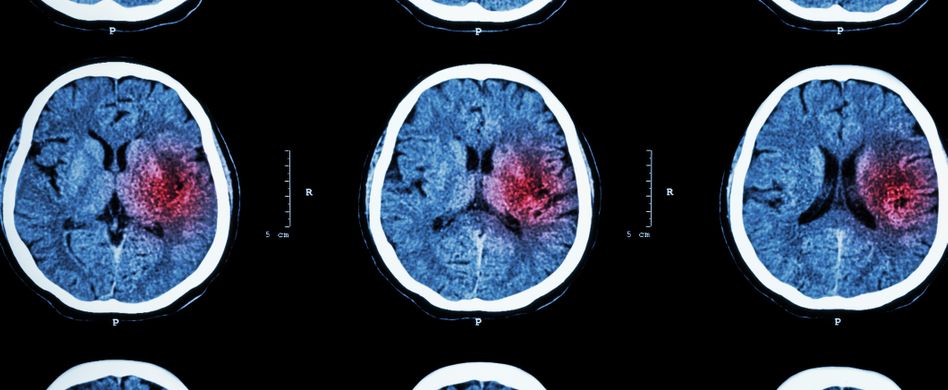

Hämorrhagischer Schlaganfall: Die Blutung im Gehirn

- Die Hirnblutung: Sie entsteht, wenn Blutgefäße direkt im Gehirn platzen und Blut ins Gehirn austritt.

Bei beiden Formen werden Teile des Gehirns schlechter mit Sauerstoff und Nährstoffen versorgt, was verschiedene Symptome wie Lähmungen, Taubheitsgefühle sowie Sprach- oder Sehstörungen hervorrufen kann. Zusätzlich drückt das austretende Blut auf das umliegende Nervengewebe und kann dieses schädigen. Bei der Subarachnoidalblutung kann es zudem zu Krämpfen kommen, die weitere Schlaganfälle auslösen.